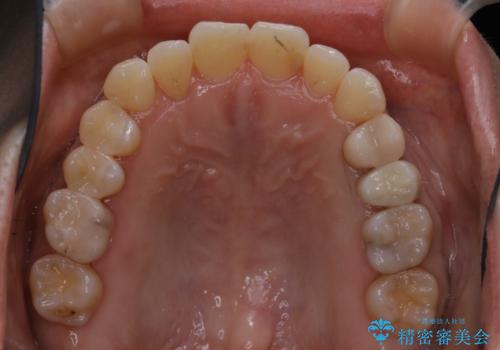

- 右上の2番目の歯が内側に入っているのと、下の前歯のがたつきが気になるとご相談にいらした方です。

上下左右の歯を後ろに動かして歯を並べるスペースを確保し、内側に入っていた歯を綺麗に並べ、前歯の中心もお顔の中心に合うようにしました。

矯正用アンカースクリューを埋入し、上下左右の歯を後ろに動かすことで歯を並べるスペースを作りました。

元々内側に倒れていた右下の奥歯は、ゴムかけを追加で行っていただくことによりしっかり起こすことが出来ました。

歯並びが綺麗になったことでモチベーションが上がり、銀歯からセラミックへのやり替えも行っております。